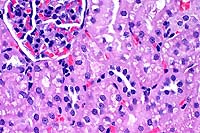

- Case 12-1. Oral mucosa with extensive ulceration (except

for lower right corner) & multifocal areas of liquefactive

necrosis surrounded by both suppurative and granulomatous inflammation.

20x

obj

- Case 12-1. Oral mucosa. Necrotic foci are centered

on an eosinophilic coagulum composed of necrotic cells and denatured

protein which forms picket fense-like radial projections (Splendore-Hoeppli

phenomenon). This material is surrounded by myriad eosinophils,

fewer neutrophils, and more distant accumulations of epithelioid

macrophages.

- Conference Note: This pedunculated to polypoid lesion

is covered by an extensively ulcerated stratified squamous nonkeratinizing

epithelium. Within the mass, there are multifocal to coalescing

nodular aggregates of eosinophils and macrophages that palisade

around degenerate, fragmented, and sometimes hyalinized, bundles

of collagen. Lymphocytes and plasma cells surround the eosinophilic

granulomatous nodules, and immature fibrous connective tissue

forms the peripheral boundaries of these inflammatory foci.